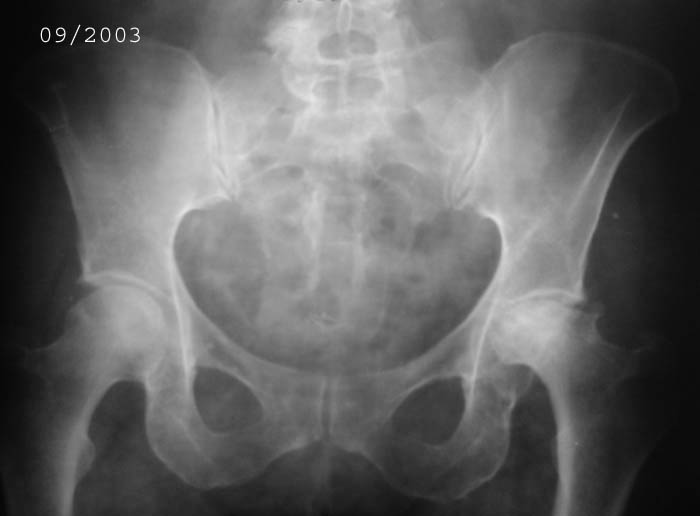

Уважаемые коллеги! Прошу Вас оказать консультативную помощь. Женщина, 44 года, инвалид 3 группыДиагноз: СКВ, асептический некроз головок обеих бедернных костей, двусторонний артроз 3-4 ст., болевой синдром, приводящая контрактураправого тазобедренного сустава, хронический волчаночный гепатит, спленомегалия, анемия, СКВ с 2002 года (подтверждена наличием lupus-клеток), получала специфическую терапию, медрол 16 мг/сут. Боли в левом тазобедренном суставе появились в сентябре 2003 года. Динамика отражена на рентгенограммах. В марте 2004 года - синдром Мэллори-Вейса, кровотечение остановлено эндоскопически. Объективно: кожа бледная, пастозность, отечность лица, высыпания на лице практически отсутствуют. Печень +6 см, селезенка не пальпируется. АД140/80, пульс 100, дыхание 15.

Ходит с тростью, хромота. Объем движений в суставах: справа - сгибание 90, разгибание 170, отведение 0, приведение 20, внутренняя ротация 15;слева - сгибание 90, разгибание 180, отведение 0, приведение 20, внутренняя ротация 0, наружная ротация 20. ЭКГ - отклонение ЭОС влево, гипертрофия левого желудочка, дистрофические изменения миокардаОбщий анализ крови: Э. 3,6, Hg 100, цп. 0,83, л.7,3, э.1, п.3, с.72, л.19, м.5, СОЭ 5 Общий анализ мочи: объем 120,0, уд.вес 1008, желтый, р-ция кислая, сахар/белок/цилиндры нет, эпителий и эритроциты единичные, Л.1-2, солиоксалатовые в небольшом к-ве. Биохимический анализ крови Билирубин 11,5 ммоль/л (прямой 0, непрямой 11,5), АСТ 0,24, АЛТ 0,61, протромбиновый индекс 100, рекальцификация 150, фибриноген 1,99,толерантность 8, фибринолитическая активность 240, общий белок 74,3, сиаловые кислоты 250 ед., С-реактивный белок 0. Пациентка желает выполнить тотальное эндопротезирование. Допустимо ли выполнение подобной операции? При каких условиях, дополнительной терапии? Особые предоперационные мероприятия? Личный опыт? Комментарии?Мнения? Заранее благодарю!!! С уважением, А.В.Владзимирский Донецкий НИИ травматологии и ортопедии